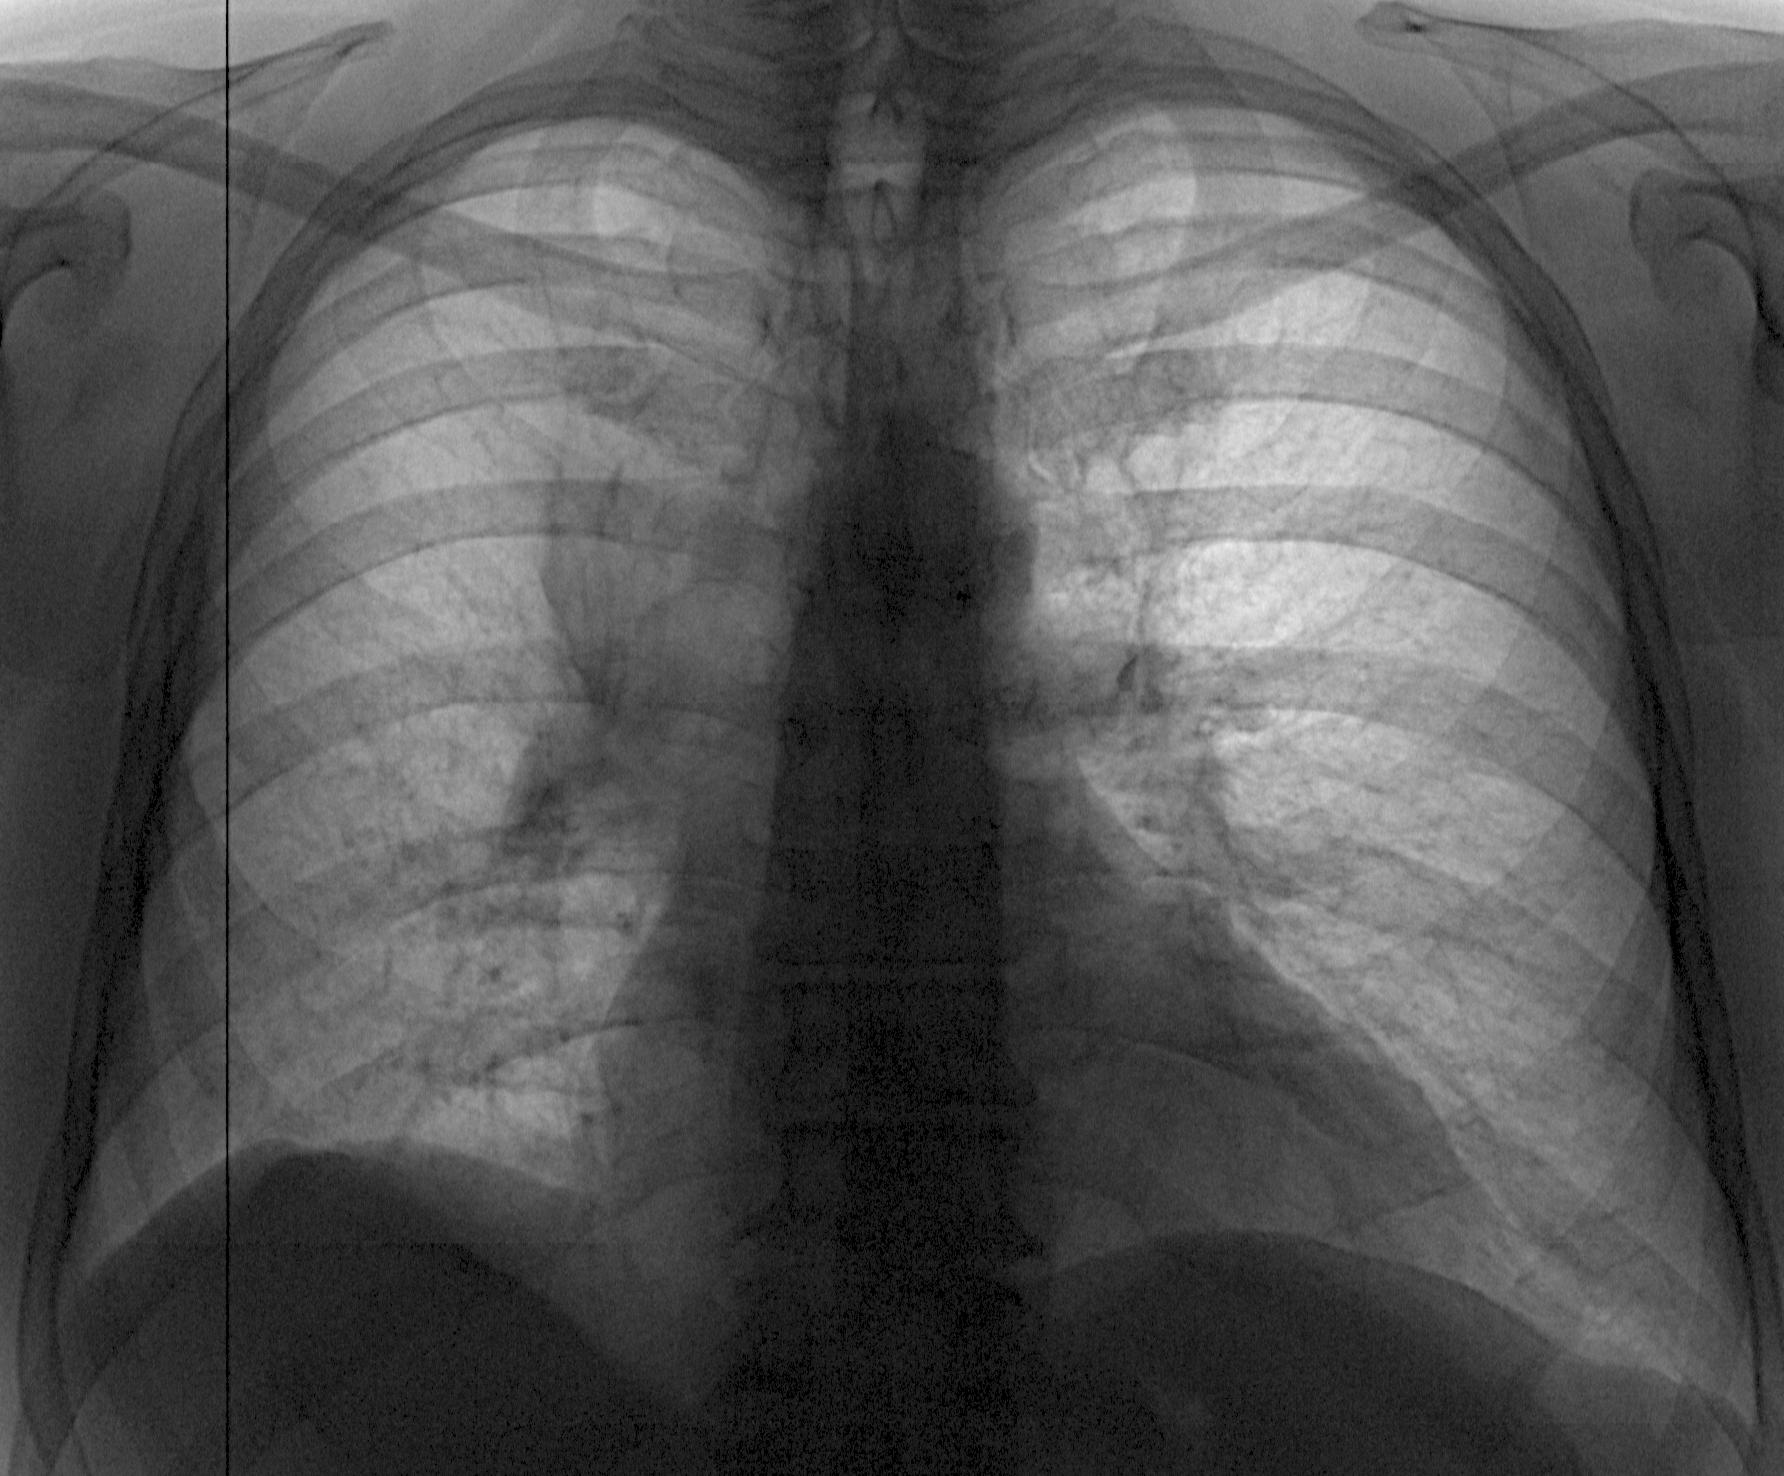

Рентген здоровых легких: примеры снимков и советы

Раздел: Сокровищница опыта